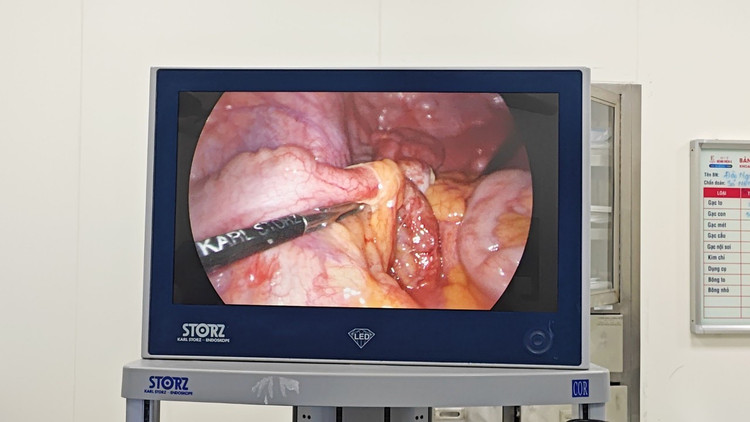

Ca phẫu thuật diễn ra khoảng 60 phút, các bác sĩ đã lựa chọn phương pháp phẫu thuật nội soi cắt ruột thừa để xử lý tổn thương cho người bệnh. Ưu điểm của phẫu thuật nội soi cắt ruột thừa giải quyết được gần như triệt để ổ mủ và cắt được ruột thừa.

Tai biến trong mổ và biến chứng sau mổ thấp và hồi phục sau mổ nhanh, an toàn cho người bệnh. Phương pháp này đòi hỏi máy móc hiện đại, trình độ chuyên môn và kỹ năng, kinh nghiệm của bác sĩ phẫu thuật được đào tạo bài bản về nội soi thực hiện.

| Phẫu thuật nội soi cho bệnh nhân - Ảnh BVCC |

Thứ hai, trong phẫu thuật, đối với người bệnh bị đảo ngược phủ tạng khi phẫu thuật các bác sĩ sẽ phải thực hiện các thao tác ngược lại như cổng trocal thao tác ngược, đặt dàn máy nội soi ngược…

Khi vào ổ bụng, các bác sĩ phát hiện toàn bộ đại tràng, gan, lách, dạ dày, ruột thừa đều đảo ngược. Ruột thừa quặt sau manh tràng nên phải tiến hành cắt ruột thừa ngược dòng.